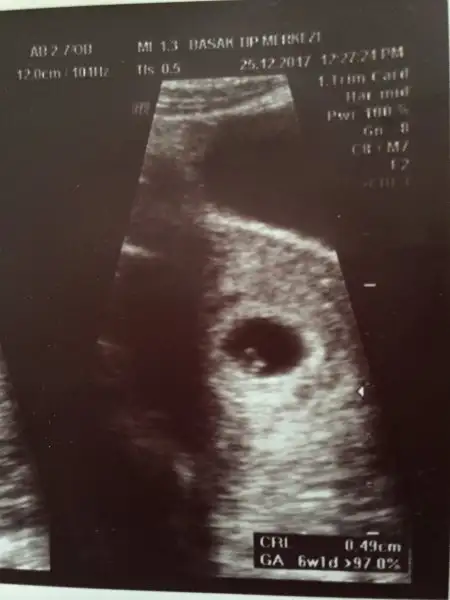

Aylardan beri vajinismus için doktora gittim. Alttanda, ultrasondanda her muayneyi genç kızlığımdan beri düzenli kontrol yaptırırım. Bugün farklı bir doktora gittim şimdiye kadar kimsenin söylemediğini söyledi. Beta artışın güzel, rahmin kalınlaşmaya başlamış, herşey şuan iyi haftaya pazartesi gel keseye bakalım. Tüm bunları anlatırken bir yandan karnıma ultrasonla bakıyordu ve çift boynuzlu rahime sahipsin doğuştan dedi. Ne desem ki...